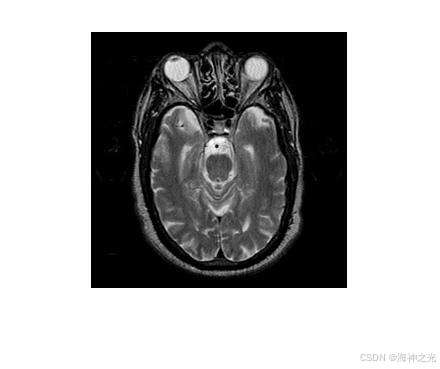

拉普拉斯金字塔(Laplacian Pyramid)是一种多尺度图像表示方法,通过高斯金字塔分解和重建实现。其核心思想是将图像分解为不同频带的子图像,低频部分保留全局结构,高频部分捕捉细节信息。在多模态医学图像融合中,拉普拉斯重分解利用不同模态(如CT、MRI、PET)的互补性,通过频域分离与重组提升融合质量。

⛄三、运行结果